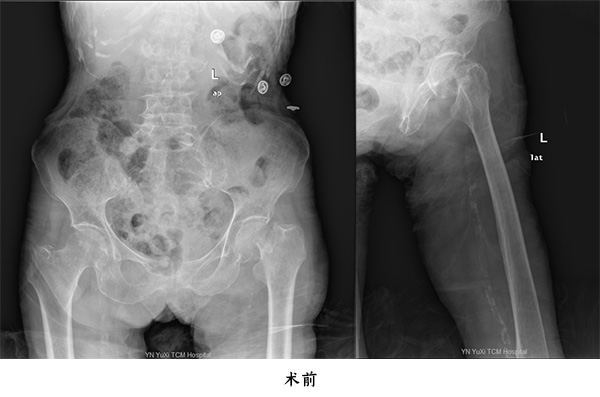

第一位為百歲老人張老太,因?yàn)樵诩抑凶呗窌r跌倒致傷左髖部,傷后至當(dāng)?shù)蒯t(yī)院就診,拍片檢查結(jié)果示左股骨頸骨折,后轉(zhuǎn)至我院住院治療;第二位百歲老人為王大爺,也是因?yàn)樵诩议T口走路跌倒致傷右髖部,在當(dāng)?shù)蒯t(yī)院就診拍片并診斷為右股骨頸骨折,后轉(zhuǎn)至我院住院治療。

由于高齡老人往往基礎(chǔ)病較多,全身器官如心、腦、肺等功能欠佳,如果施行手術(shù)風(fēng)險極高,如果在病人管理上某一個環(huán)節(jié)出現(xiàn)問題就會隨時危及生命,高齡股骨頸骨折患者,如果采用保守治療,因?yàn)殚L期臥床而產(chǎn)生一些致命性的并發(fā)癥,入住玉溪市中醫(yī)醫(yī)院骨傷二科(關(guān)節(jié)與運(yùn)動醫(yī)學(xué)科)后,經(jīng)科室團(tuán)隊(duì)詳細(xì)制定治療計(jì)劃,麻醉科會診,分別于2020年12月8日及2020年12月4日為兩名百歲老人施行人工股骨頭置換手術(shù),手術(shù)過程順利,通過該手術(shù),兩名百歲老人再次站起來下地步行,均順利康復(fù)出院。